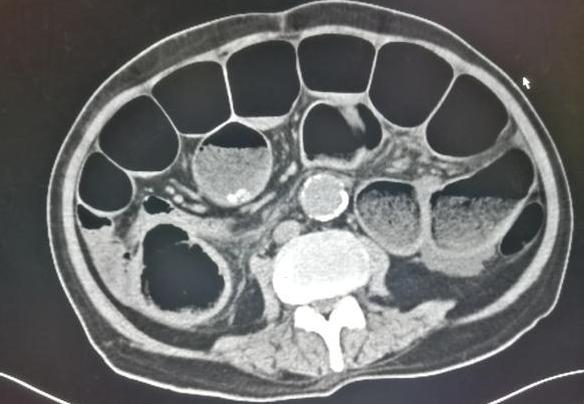

这位老人70多岁,结肠功能减退,肠内容物排空慢,潴留时间长,一直没有大便。

硬结的粪块堵死了肠道,引起低位肠梗阻,大量肠胀气。

经过多次灌肠才缓解,住院一个礼拜。